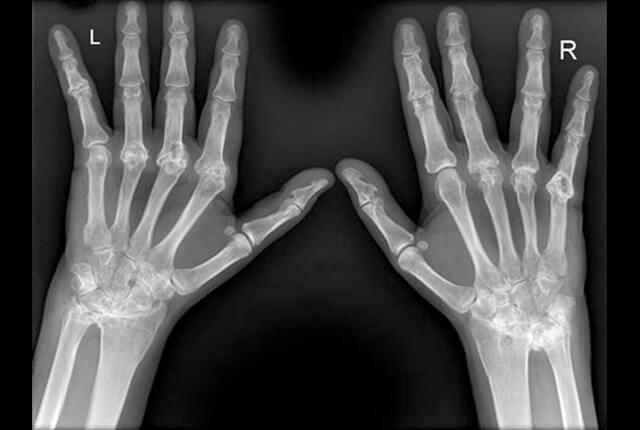

単純X線:骨びらん、関節破壊